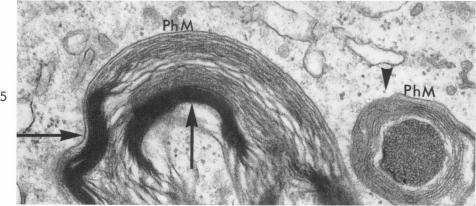

Phagocytosis and regeneration of myelin in an experimental leukoencephalopathy.

Am J Pathol. 1964 Apr;44(4):565-83.

PMID:5877506

原文链接:https://pmc.ncbi.nlm.nih.gov/articles/PMC1907034/